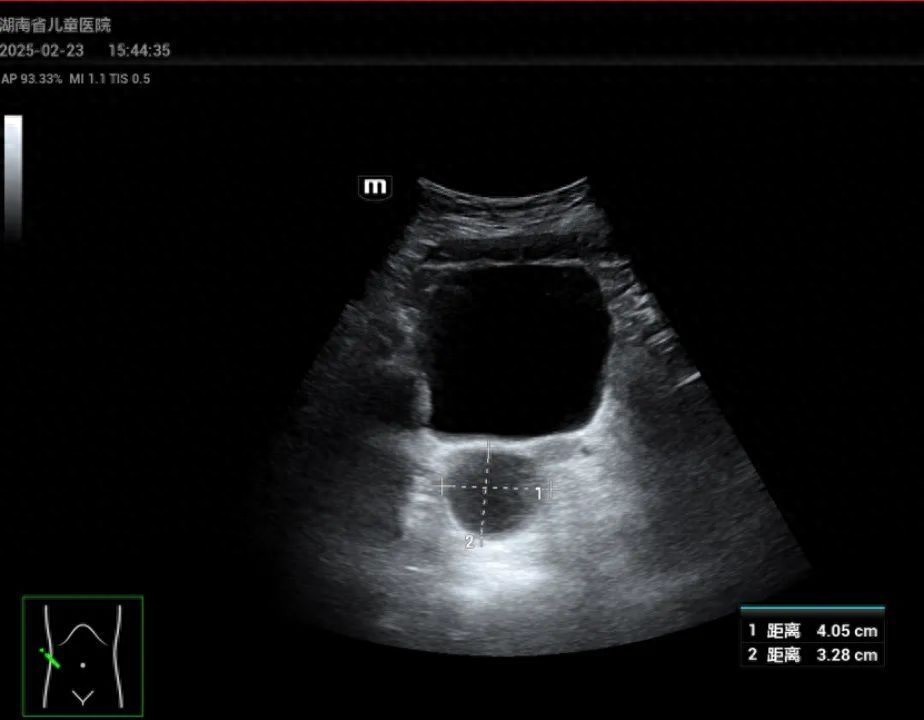

通讯员 | 柳娜 记者 | 任弯湾家住望城的陈女士怎么也想不到,年仅6岁的女儿晗晗(化名)竟来了月经。最近,陈女士将孩子带到湖南省儿童医院肝病内分泌科就诊,经过副主任医师谭艳芳体查发现,晗晗乳房已有发育变大迹象,B超报告显示“盆腔偏右侧囊性包块,左侧卵巢可见多个直径大于4mm的卵泡,双侧乳房可见腺体回声”。谭艳芳告诉陈女士,孩子是外周性性早熟,可能需要手术治疗。近段时间,该科连续接诊了4例6-8岁女童来月经的病例,均以“阴道出血”为主要症状就诊。经详细询问病史、体格检查及相关辅助检查,最终考虑诊断为性腺肿瘤或囊肿所致的外周性性早熟。湖南省儿童医院肝病内分泌科副主任医师谭艳芳表示,外周性性早熟又称假性性早熟,是由于各种原因引起的体内性甾体激素升高至青春期水平,从而导致女孩7岁半前乳房发育,10岁前来月经,男孩9岁前出现第二性征发育的一种内分泌疾病,但不伴有下丘脑-垂体-性腺轴的启动。值得注意的是,4例患儿盆腔B超均提示存在囊性包块。谭艳芳表示,当女孩单纯出现阴道出血时,要注意排除阴道感染、异物或肿瘤等,需进一步排查病因。谭艳芳提醒,家长要密切关注孩子的生长发育情况,如果发现女孩7岁半前乳房发育,10岁前来月经,男孩9岁前出现睾丸增大、阴茎增长、阴毛生长等第二性征发育迹象,应及时带孩子到医院就诊。平时避免孩子接触含有激素的食品、药品和化妆品;养成良好的生活习惯,保证充足的睡眠,避免熬夜,控制体重,避免肥胖。营造良好的家庭氛围,避免给孩子过大的精神压力。儿童性早熟是一种可以治疗的疾病,早发现、早诊断、早治疗至关重要。部分性早熟可能与肿瘤等疾病相关,需引起重视。如果孩子出现疑似性早熟的症状,请及时带孩子到正规医院就诊,进行专业的诊断和治疗,以免耽误病情,影响孩子的身心健康。来源: 潇湘晨报